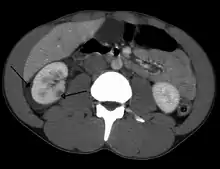

Abdominal trauma resulting in a right kidney contusion (open arrow) and blood surrounding the kidney (closed arrow) as seen on CT

The kidneys may also be injured; they are somewhat but not completely protected by the ribs.[6] Kidney lacerations and contusions may also occur.[13] Kidney injury, a common finding in children with blunt abdominal trauma, may be associated with bloody urine.[13] Kidney lacerations may be associated with urinoma or leakage of urine into the abdomen.[4] A shattered kidney is one with multiple lacerations and an associated fragmentation of the kidney tissue.[4]